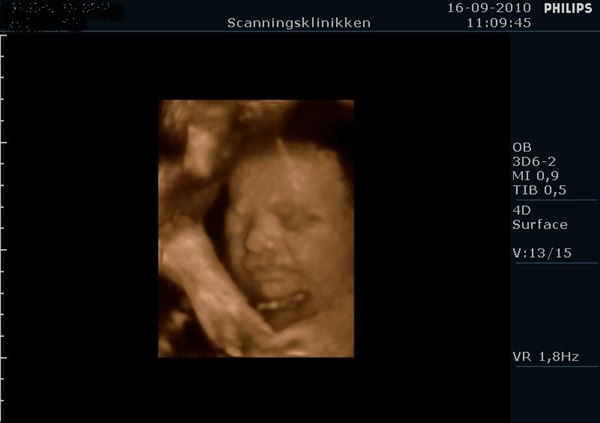

Det så bare så skægt ud med den hikke, og tror nok det kom med på dvden i starten hvor hun lavede 2D...

Men ja, hun ser bare så dejlig ud, og vil bare så gerne have hende ud med det samme, men hun skal jo lige blive lidt længere alligevel

Ej hvor sjovt, smiler.. Det er da ret specielt at have på dvd

Hehe.. ja, efter sådan en 3D/4D har man bare lyst til at føde og få den lille ud i sine arme